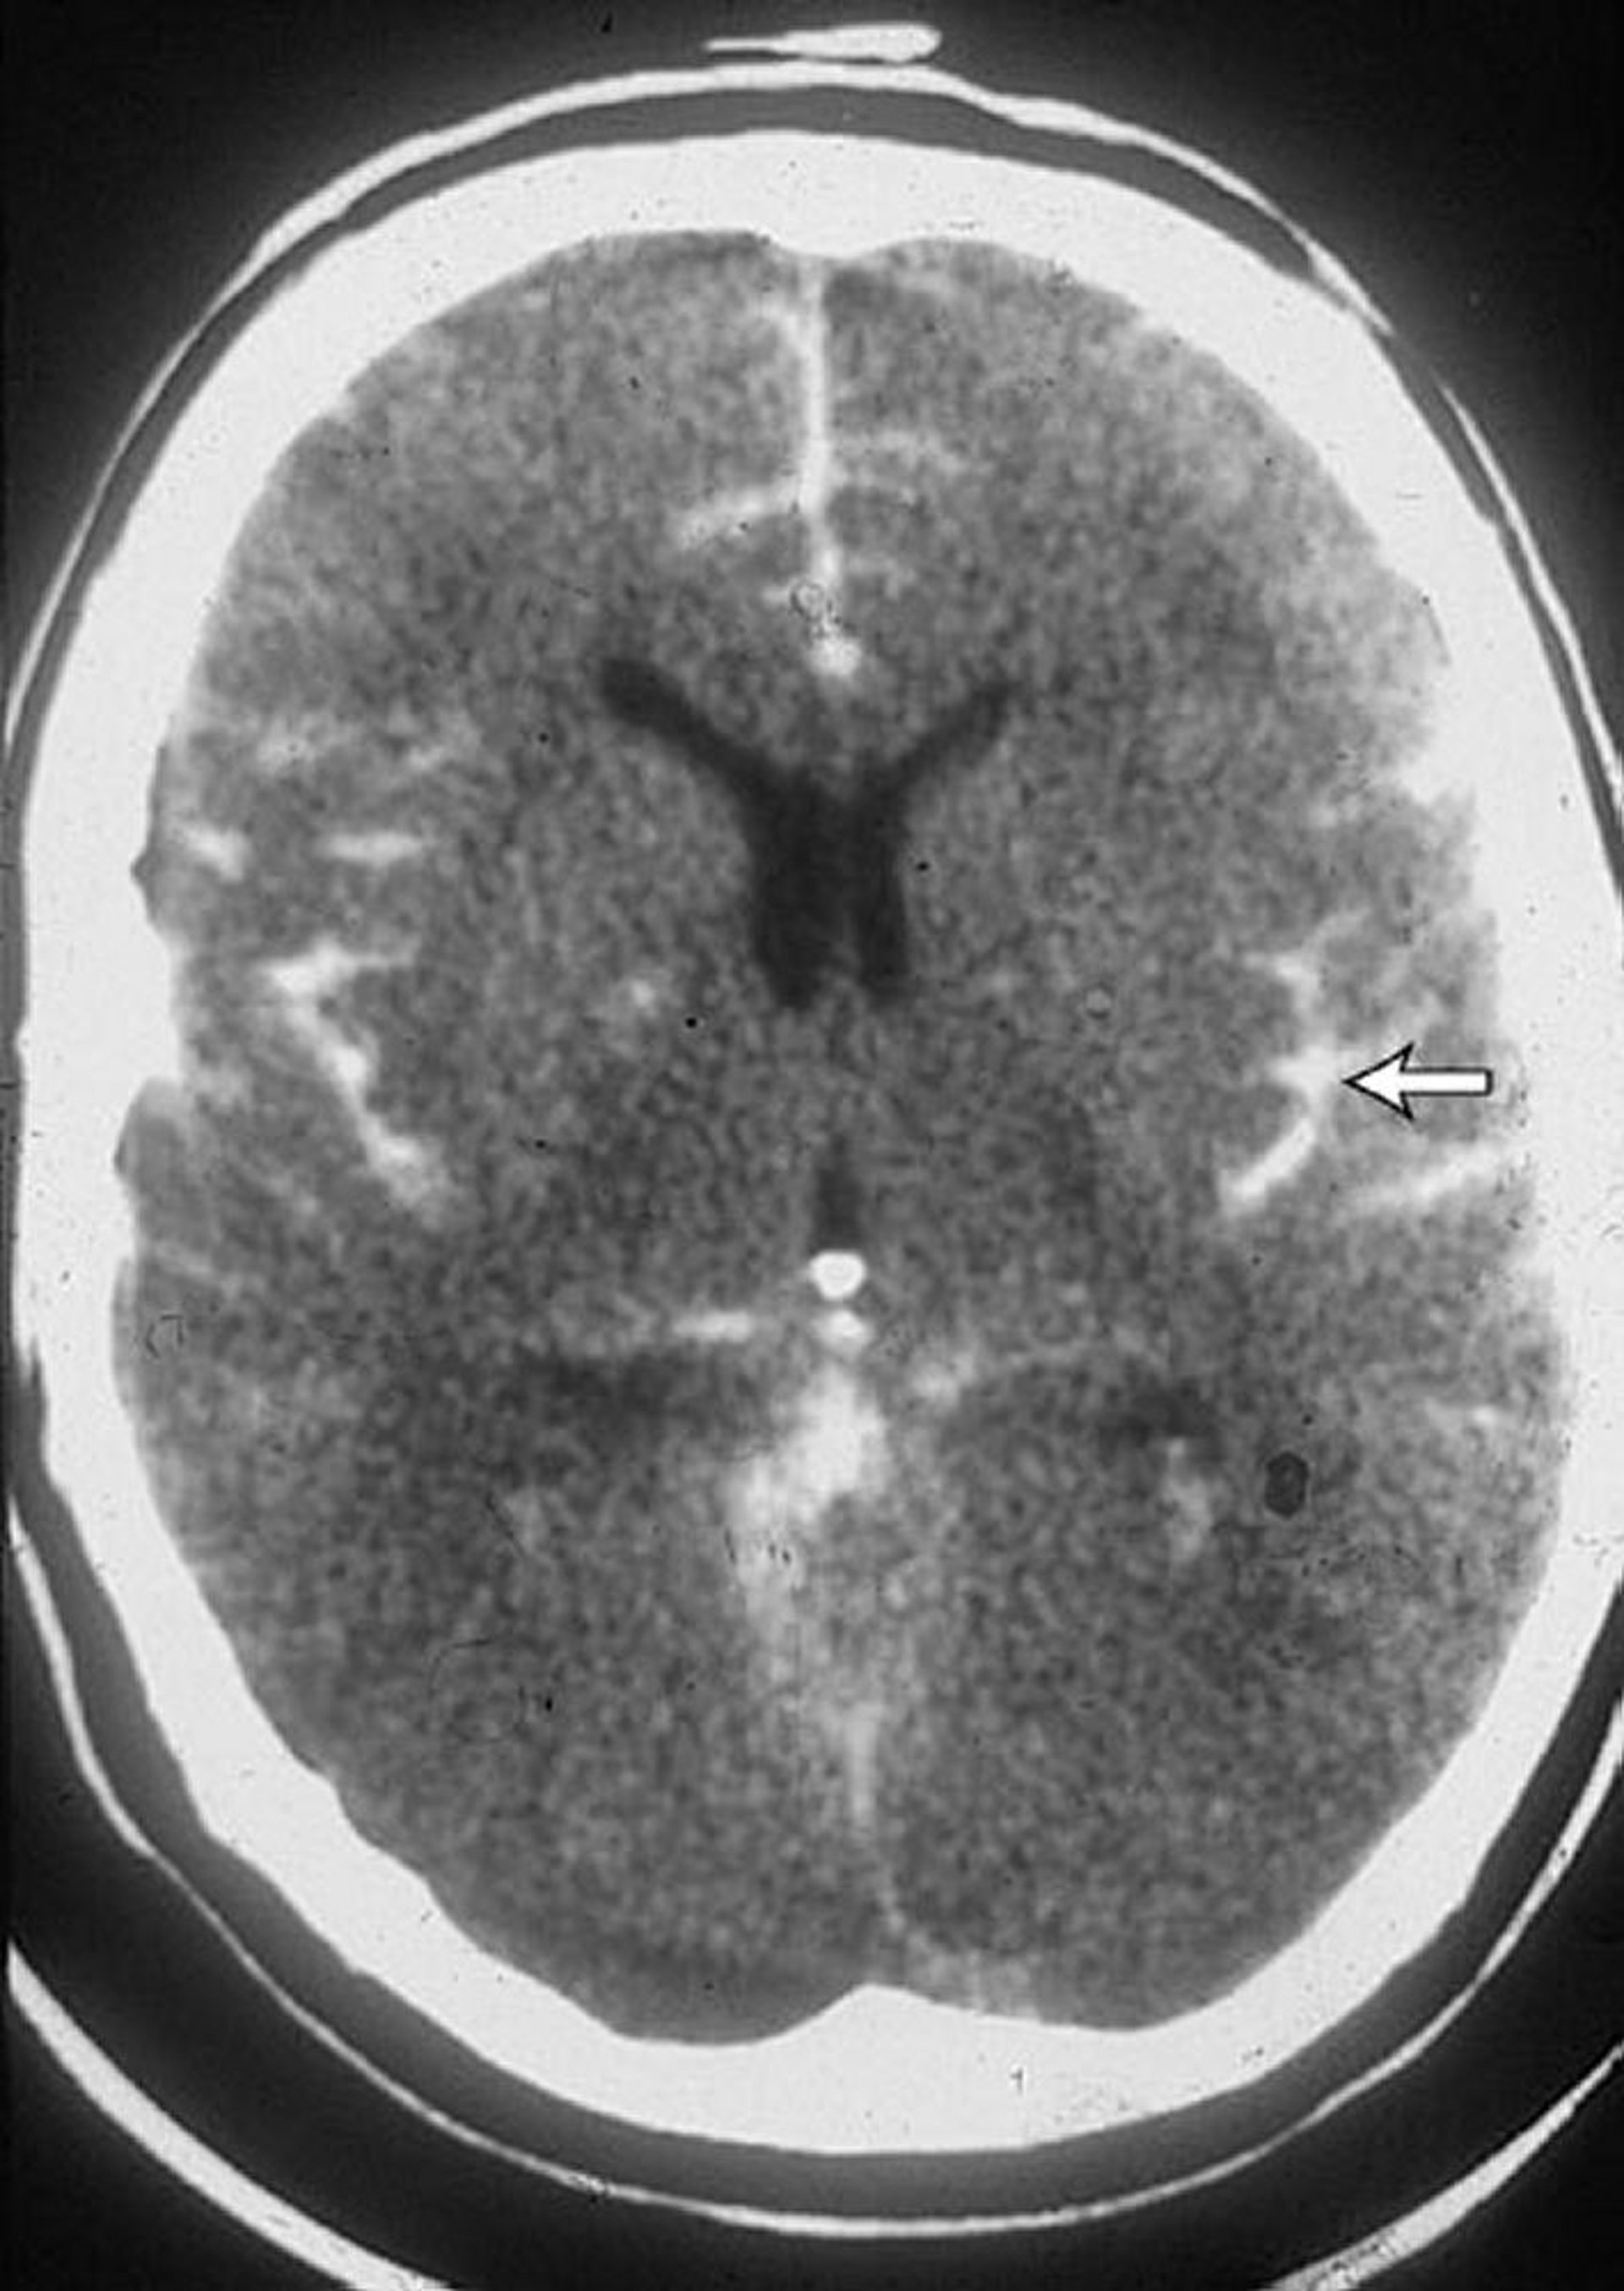

Subarachnoid Hemorrhage

This CT scan in a patient with a subarachnoid hemorrhage shows blood in the sulci (arrow). Blood is often also seen in the ventricles.

By permission of the publisher. From Lenaerts M, Couch J. In Atlas of Clinical Neurology. Edited by RN Rosenberg. Philadelphia, Current Medicine, 2002.